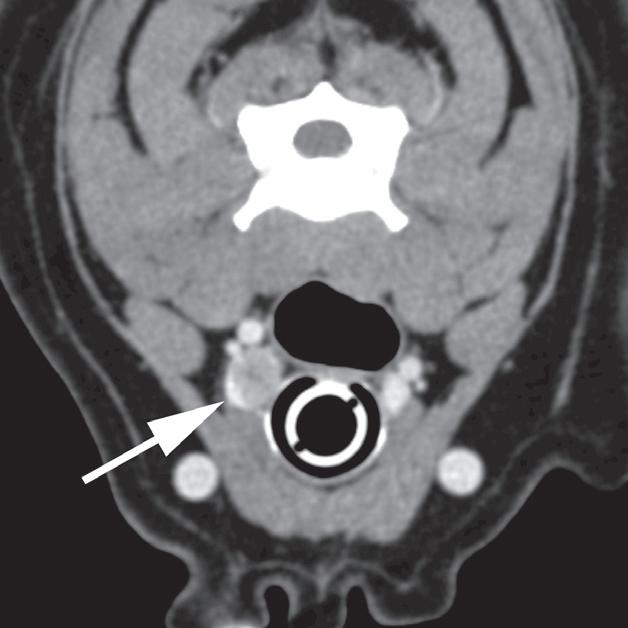

Badanie wykonano u 12-letniej, kastrowanej samicy labradora retrievera z wcześniej zdiagnozowanymi masami płucnymi i szyjnymi. W badaniu USG uwidoczniono kulisty, hipoechogeniczny guzek w obrębie prawego płata tarczycy (a). W TK masa jest nieznacznie hipodensyjna w obrazach bez wzmocnienia (b – strzałka). Lewy płat tarczycy ma prawidłową wielkość i jest hiperdensyjny (b – grot strzałki). Masa ulega umiarkowanemu wzmocnieniu po podaniu środka kontrastowego, jednak w mniejszym stopniu niż sąsiedni prawidłowy miąższ tarczycy (c – strzałka) i jej przeciwległy płat. W obrazach w rekonstrukcji grzbietowej w projekcji MIP po podaniu środka kontrastowego uwidoczniono przebieg obu tętnic szyjnych wspólnych dogrzbietowo względem płatów tarczycy (d – groty strzałek). Cieńszy przekrój MIP wykluczający tętnice szyjne ukazuje płaty tarczycy (e – strzałki) oraz lokalizację masy w obrębie prawego płata (e – grot strzałki). Biopsja wycinkowa wykazała raka tarczycy o utkaniu litym i pęcherzykowym z naciekaniem naczyń i torebki